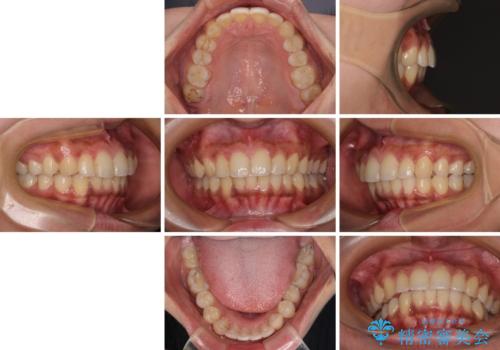

深い咬み合わせと前歯のデコボコ インビザラインによる矯正治療

- 前歯のデコボコと、食いしばりやすい咬み合わせを気にして来院された患者様です。

骨格的に下顎骨が左側に偏位しており、インビザラインでの矯正治療では奥歯の咬みにくさが残る仕上がりが懸念されましたが、新幹線での通院となるため、来院回数の少ないインビザラインでの治療を希望されました。

リスクをご説明した上で、インビザラインにより気になっている叢生と深い咬み合わせを改善していくこととしました。

治療途中では、左右ともに奥歯が咬みにくい状態が続き、問題なく噛めるようになるまでに長期間を要しました。

一方で、デコボコや下顎の前歯が隠れてしまうほどの深い咬み合わせはしっかりと改善されました。